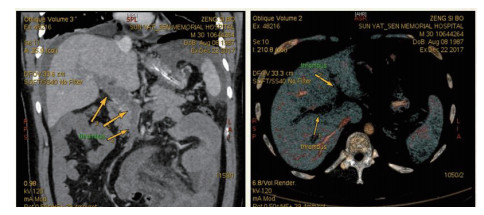

1 资料与方法患者男,30岁,因“腹胀、腹痛6 d,高热1 d”于2017年12月11日由广州南沙区中心医院转诊收入中山大学孙逸仙纪念医院全科医学科。患者本次起病前无明确病因或明显诱因。患者以左上腹轻微胀痛起病,进行性加重。南沙区医院查血常规:白细胞14.27×109/L,血小板50×109/L,中性粒细胞比例74.5%,嗜酸粒细胞1.02×109/L,嗜酸粒细胞比例7.2%。全腹CT+CTA提示:门静脉左右主干及其小分支栓子形成。后在3 d内连续复查血常规,提示血小板进行性下降,由50×109/L相继降至35×109/L、18×109/L;(嗜酸粒细胞计数及比例未能提供),并出现高热(体温39.5℃),因病情危重,遂转诊本院。入院时患者精神疲乏、高热,腹部胀痛难忍,伴有咳嗽。查体:体温38.6℃,心率87次/min,血压102/76 mmHg,指尖血氧饱和度90%~91%。双肺呼吸音粗,双肺均可闻及小水泡音。腹部稍膨隆,叩诊鼓音,左上腹及脐周轻压痛,无反跳痛。听诊肠鸣音减弱,约1~2次/min。当天查血常规示白细胞11.85×109/L,血小板23×109/L,中性粒细胞比例58.1%,嗜酸粒细胞3.5×109/L,嗜酸粒细胞比例29.5%。凝血常规提示:PT 15.9S,PTA 51.1%,PT/R 1.39,Fbg 1.59 g/L,PTINR 1.39,APTT 35.2 s,D-二聚体114.36 mg/L FEU(参考值范围0~0.55 mg/L FEU)。胸部+全腹部CT+CTA示“门静脉主干及左、右支、肠系膜上静脉近端栓子形成;腹主动脉及左侧髂总动脉小附壁血栓;左肺上叶尖后段、左肺上叶下舌段、右肺中叶及双肺下叶炎症;乙状结肠两段节段性管壁增厚,建议排外占位性病变;腹水、盆腔积液,大网膜炎性病变可能性大”。每日复查血常规,发现血小板进行性下降,最低至15×109/L(参考值范围125~350×109/L),嗜酸粒细胞计数及比例进行性升高,分别达到8.07×109/L(参考值范围0.020~0.52×109/L)和51.1%(参考值范围0.4-8.0%)。每日复查凝血常规亦提示凝血指标不断恶化,纤维蛋白原最低降至0.63 g/L。在予禁食、“美平(美罗培南)”抗感染、输注纤维蛋白原及血小板、维护水电解质平衡及营养支持的积极治疗的同时,还积极完善了以下检查寻找病因:①血液系统方面:血浆鱼精蛋白副凝实验:阳性(+);凝血功能实验:PT 15.5S↑,PTA 47.8%↓,PT/R 1.35↑,PTINR 1.36↑,APTT 40.4 s↑,AT-Ⅲ 57.7%↓,F-VII 32.8%↓,F-Ⅷ 68.1%↓,F-X 68.0%↓,F-XII 24.0%↓;纤维蛋白降解产物:381.4 mg/L↑;血栓弹力-血小板图:R时间10.3 min↑;角度18.5度↓;最大血块强度13.2 mm↓;MA(ADP)值5.6 mm↓。骨髓病理学:嗜酸性粒细胞增多(43%),巨核细胞减少(7个)。慢淋/淋巴瘤表型分析:获取和分析细胞数5.0万;粒细胞区百分比82.6%;淋巴细胞区百分比9.4%;单核细胞区百分比2.0%;CD45dim细胞区百分比1.3%;有核红及细胞碎片区域百分比4.6%。ETV6/PDGFRB融合基因、FIP1L1/PDGFRA融合基因(—)。骨髓细胞学病理结果:符合嗜酸细胞增多症;②消化系统检查:大便细菌培养鉴定及药敏提示无志贺、沙门菌生长,有真菌生长;大便难辨梭菌毒素检测(—);粪便找寄生虫、找阿米巴、寄生虫七项均为(—);消化肿瘤系列提示CA-125 244.8 U/mL↑;腹腔穿刺术穿出“血性腹水”,腹水CA-125 1006.0 U/mL↑,腹水找癌细胞(—);复查腹部CT+CTA:乙状结肠两段节段性管壁增厚,建议进一步检查;排外占位性病变;遂行PET-CT:提示全身未见明确恶性征象。行电子结肠镜示:内镜诊断:(1)回肠末段炎症;(2)乙状结肠炎症;(3)内痔。钳取组织送病理,提示:标本①(回肠末端)黏膜组织呈慢性炎,伴糜烂,一些嗜酸性粒细胞浸润(约35个/HPF);②(乙状结肠)黏膜组织呈慢性炎,伴糜烂,个别嗜酸性粒细胞浸润(约4个/HPF)。③风湿免疫系统方面:免疫八项、风湿四项:C反应蛋134.0 mg/L,余未见异常;总IgE 170 IU/mL↑;抗ENA抗体、狼疮两项、血管炎两项、免疫球蛋白G4、抗心磷脂抗体三项均为阴性;④其他感染病原学检查:乙肝、肝炎系列、性病三项、痰找抗酸杆菌、T-spot实验、流行性出血热、登革热抗体、登革热病毒NS1抗原、外斐氏试验、肥达氏试验、痰结核培养、骨髓培养、血液细菌、血液厌氧菌培养均为阴性。经过上述检查,初步考虑“特发性嗜酸性细胞增多症”,于12.15开始予“甲泼尼松龙40 mg静滴, 1次/d”及“低分子肝素0.6 ml皮下注射, 1次/d”抗炎抗凝治疗。患者病情及检验指标有所好转,热退、腹胀减轻,血常规提示血小板升至49 ×109/L,嗜酸粒细胞计数和比例均下降至正常,凝血常规提示D-二聚体降至47.90 mg/L FEU。但12-22患者自行进食多量米饭后突发腹胀痛较前加重,急查血常规提示白细胞升至21×109/L,血小板再次下降至15×109/L,D-二聚体升至97.28 mg/L FEU,全腹CTA提示“门静脉主干及左、右支、肠系膜上静脉近端新发栓子形成”,遂于当日转至ICU予“尿激酶20万U+肝素钠1250 U”溶栓治疗后予“低分子肝素0.6 ml皮下注射, 1次/12 h”序贯抗凝治疗。后患者病情渐渐稳定,至2018-1-18患者在“甲泼尼松龙12 mg口服, 1次/d”及“立伐沙班20 mg口服, 1次/d”的维持治疗下,血小板、嗜酸粒细胞计数及纤维蛋白原均回复正常,D-二聚体下降至3.52 mg/L FEU。但遗憾的是,此时患者再次进食大量米饭,约1 h后突发腹痛、气促,急行胸片+腹平片提示:“双侧膈下游离气体,考虑胃肠道穿孔可能;双下肺少许炎症,少量胸腔积液;腹部多量积气伴肠腔扩张”。遂即送手术室行全麻下“腹腔镜探查+坏死空肠切除+大网膜切除+肠系膜上动脉探查+空回肠双腔造口术”,术后病理提示标本①(大网膜)脂肪组织,部分坏死,合并慢性炎,伴一些中性粒细胞浸润,较多泡沫样组织增生,未见明确血栓,未见恶性改变。②(部分空肠)肠壁组织,部分肠壁全层坏死,合并慢性炎,肉芽组织增生,未见明确血栓,未见恶性改变。免疫组织化学:CD38浆细胞(+)、IgG(+)、IgG4(﹣)。术后继续予“立伐沙班10 mg/d”和“甲泼尼松龙8 mg/d”口服治疗,并于2018.2.4停用“甲泼尼松龙”。2.28复查全腹CTA,仍可见“脾静脉新发血栓,门静脉及肠系膜上静脉血栓较前好转”。3.20行空回肠双腔造瘘管泛影葡胺造影术提示“双腔造瘘管通畅,右中下腹小肠蠕动尚可,结肠各段及直肠通畅,未见对比剂外漏征象”。但患者合并了严重的短肠综合征,致严重低钾低钠血症和继发的代谢性脑病,病情再度转危。继续纠正电解质紊乱、补充营养,最终病情好转后于4.11行“造瘘口回纳修补术”。随访半年,患者仍口服“立伐沙班10 mg/d”抗凝治疗,复查血常规、凝血常规等各项指标均正常,但营养状况较差。

| 图 1 全腹CTA(2017-12-22):门静脉及肠系膜上静脉血栓形成 |